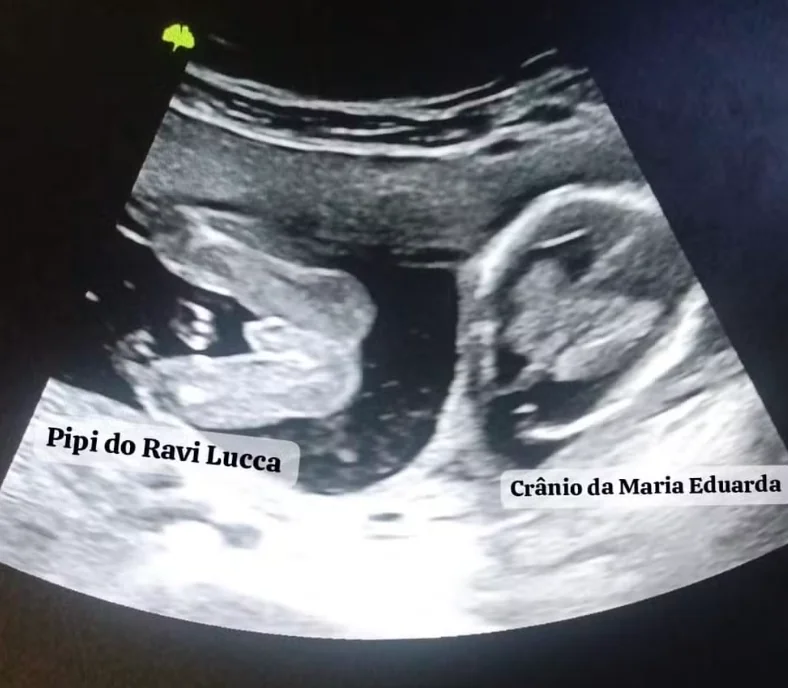

Focada na carreira como editora de laudos hospitalares, Paloma foi surpreendida novamente em setembro de 2024: estava grávida de gêmeos — um em cada útero, cada um com sua placenta e bolsa. “Levei um susto”, lembra. No primeiro ultrassom, apareceu apenas um bebê; uma semana depois, o exame revelou o segundo. O marido duvidou: achou que ela tinha editado a imagem.

Ravi Lucca nasceu primeiro, precisou ser reanimado e foi levado à UTI Neonatal. Em seguida, veio Maria Eduarda, rapidamente encaminhada ao berçário. “Foi a minha primeira cesárea. Nunca vou esquecer pelo sofrimento e medo”, diz Paloma. Hoje, ambos se recuperam bem.